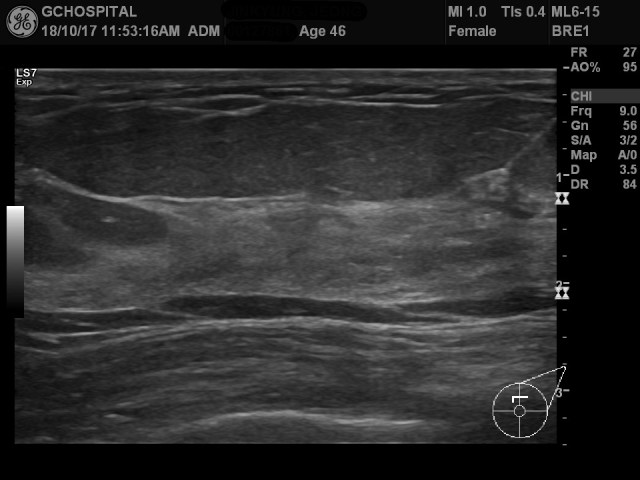

00127861_US_20181017354_20181017_002

건강검진을 위해 내원하신 분의 유방초음파 영상입니다. 지방조직과 유방실질의 에코음영은 서로 명확하게 구분이 되지만, 유방실질 내에 유도과(mammary duct)나 지방조직의 fat lobule사이에 존재하는 막은 잘 보이지 않습니다.

영상의 오른쪽에 보면 parameter가 적혀있는데, dyamic range가 84데시벨로 맞춘 영상입니다.